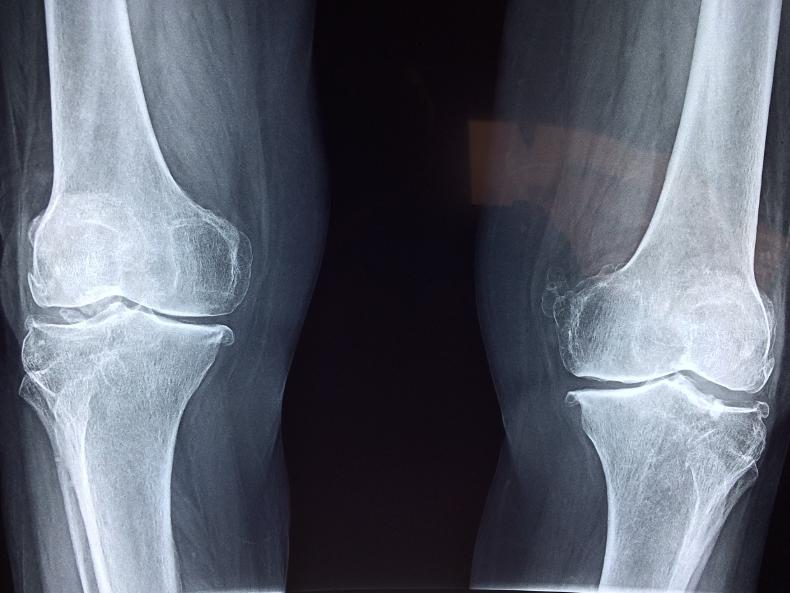

2) 무릎 관절

•증상: 계단 오르내리기 어려움, 무릎이 붓거나 삐걱거리는 소리 발생.

장시간 걷거나 움직인 후 통증이 심해질 수 있습니다.

•관련 관절염: 퇴행성 관절염, 통풍성 관절염.